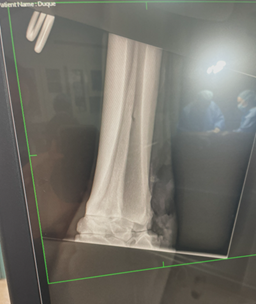

He was injured in a pasture accident, likely fighting over the fence with another gelding. Initial radiographs showed no fracture, which is not uncommon—fractures can take time to become visible. Meanwhile, a small cut at the site of the wound became infected, leading to cellulitis. He was put on oral antibiotics, and new radiographs revealed a fracture of the lateral splint bone in his right hind leg.

Duque went for surgery in Phoenix. Because of the cellulitis and location of the fracture, the procedure included the removal of the entire splint bone, including the section forming part of the hock joint. He remained in the clinic for a week of IV antibiotics, where the infection was stabilized. He then went to Miller Equine Rehab in Cave Creek for three months of intensive therapy, including cold saltwater spa treatments, shockwave therapy, and pulsed electromagnetic field (PEMF) therapy. The prognosis was poor. Because the entire splint bone was removed and complicated by infection, several veterinarians told me that Duque might never return to soundness.